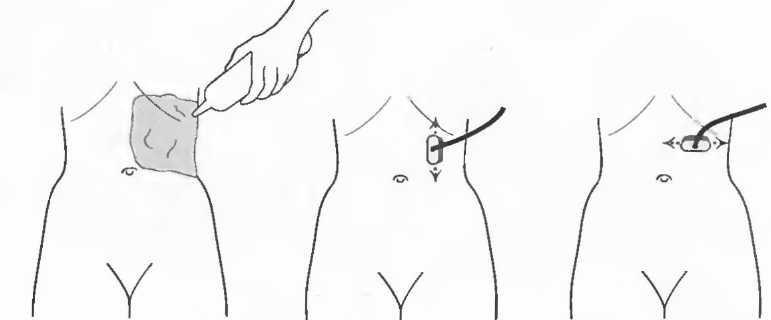

1. Подготовка

Пациент не должен пить и есть в течение 8 ч перед исследованием. Если жидкость необходима для предотвращения дегидратации, можно давать пациенту только воду. При острой симптоматике исследование можно проводить без подготовки. Детям, если позволяют клинические условия, пища и вода не даются в течение 3 ч до исследования.

При более углубленном исследовании, если нет клинических противопоказаний, может быть полезным дополнительный прием воды, особенно при исследовании поджелудочной железы, нижних отделов живота и таза.

2. Положение пациента. Пациент может лежать в удобной позе на спине. Под голову можно положить маленькую подушку, в случае выраженного напряжения передней брюшной стенки подушечку можно поместить также под колени пациента.

Намажьте живот гелем.

Пациенту разрешается дышать спокойно, однако при исследовании отдельных органов требуется задержка дыхания на вдохе.

3. Выбор датчика. Используйте датчик 3,5 МГц для взрослых и датчик 5 МГц для детей и худых взрослых. Предпочтительны конвексные или секторные датчики.